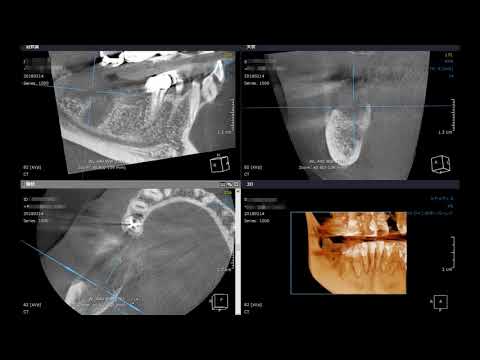

従来のレントゲンでは重なって見えなかった骨の厚みや、神経・血管の位置関係を、あらゆる角度からスライス画像として正確に確認することができます。この「奥行き」の情報こそが安全な外科処置の鍵となります。

下の顎の骨は、実は非常に複雑で個人差の大きい形状をしています。特に、舌側の下部が、まるでえぐり取られたように内側に大きく凹んでいる方が驚くほど多くいらっしゃいます。

この断層画像を見なければ、この「内側の凹み」は決して分かりません。どれほど経験を積んだ歯科医師でも、通常のレントゲンだけでこれを見極めることは不可能です。

CTが普及する以前、多くの歯科医師がこの見えない凹みに気づかずに、盲目的にインプラントを埋め込み、骨からインプラント体が突き抜けてしまうといった深刻なトラブルを多発させていた時代がありました。

特に、下顎の骨に埋まっている親知らずの抜歯では、歯の根の先端と神経管との距離や位置関係を三次元的に把握することが安全な抜歯の絶対条件です。CT撮影を行うことで抜歯に伴う神経麻痺などのリスクを最小限に抑えることができます。